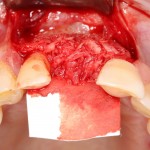

Другой вариант. Имплантируем, но существующего объема костной ткани недостаточно для получения адекватного эстетического и функционального результата:

Поэтому мы используем мембрану Geistlich BioGide и всё ту же аутокостную стружку: